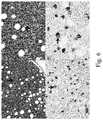

FIG. 2 illustrates various cases demonstrating the range of membrane and cytoplasmic staining in SCCHN samples at 20× magnification when labeled SP263.

II. Scoring Squamous Cell Carcinoma of the Head and Neck

SCCHN neoplastic cells labeled with the SP263 antibody are evaluated for percent positivity of the tumor cells with membrane staining at any intensity of the diaminobenzidine (DAB) signal. The immunohistochemical staining in SCCHN is membranous and/or cytoplasmic, and may be expressed homogeneously or heterogeneously throughout the neoplasm. Membrane staining can have a discontinuous or circumferential pattern. Cytoplasmic staining is generally diffuse with some cases displaying a finely granular quality.FIG. 2 illustrates various cases demonstrating the range of membrane and cytoplasmic staining in tumor cells at 20× magnification when labeled as set forth above.

The total percentage of membrane signal intensities is visually estimated and used to generate the percent tumor positive score. An isotype-matched negative control antibody is used to evaluate the presence of background in test samples and establish a staining intensity baseline.FIG. 3 illustrates an exemplary positive case with range of tumor cell membrane and cytoplasm staining. The lower left corner also shows smaller immune cells with membrane staining (arrow).